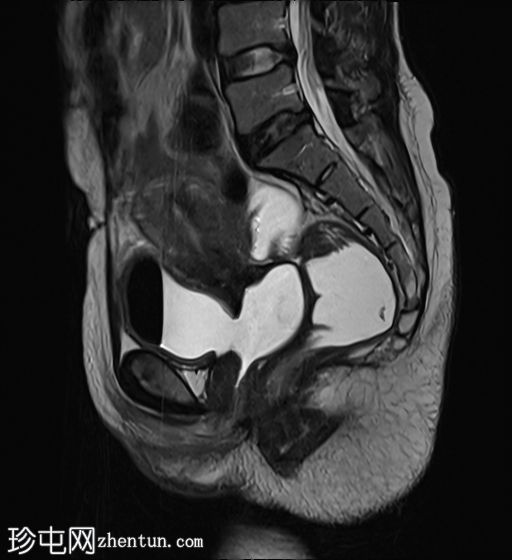

膀胱充盈后

矢状位

STIR序列

膀胱后壁与阴道前壁之间存在宽阔的瘘管。膀胱内可见气液平面。

阴道后穹窿上部与直肠中段前壁之间可见另一条较小的瘘管。在重扫描T2加权像上也可见。

此外,还有一个较小的直肠阴道瘘,容易被忽略,但直肠扩张并伴有液体信号强度(未注射凝胶)提示存在直肠阴道瘘。给予患者饮水以充盈膀胱,薄层扫描清晰地显示了狭窄的瘘管。

当膀胱未完全充盈时,直肠阴道瘘不明显,直肠内液体量也很少。然而,膀胱充分充盈后,直肠扩张,瘘管清晰可见。这凸显了在怀疑存在短瘘时,通过注入外源性液体或增加口服液体摄入量等方法确保操作技术正确的重要性,正如本病例所示。